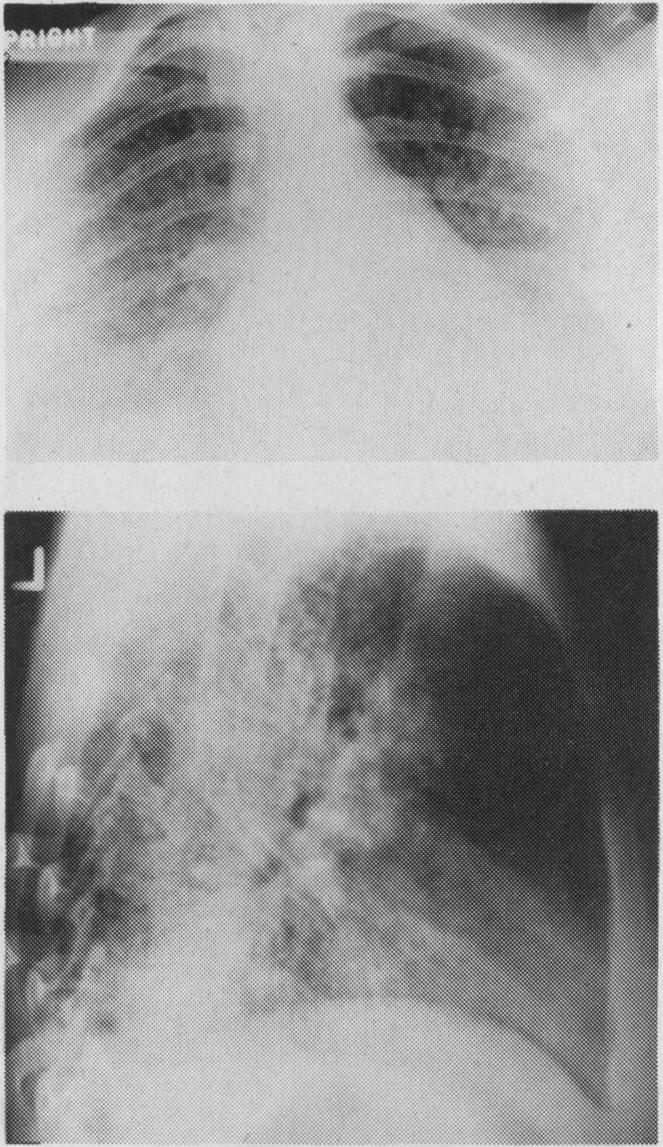

Extensive pulmonary infiltration by leukemic blast cells treated with irradiation.

Can Med Assoc J. 1983 Feb 15;128(4):424-6.